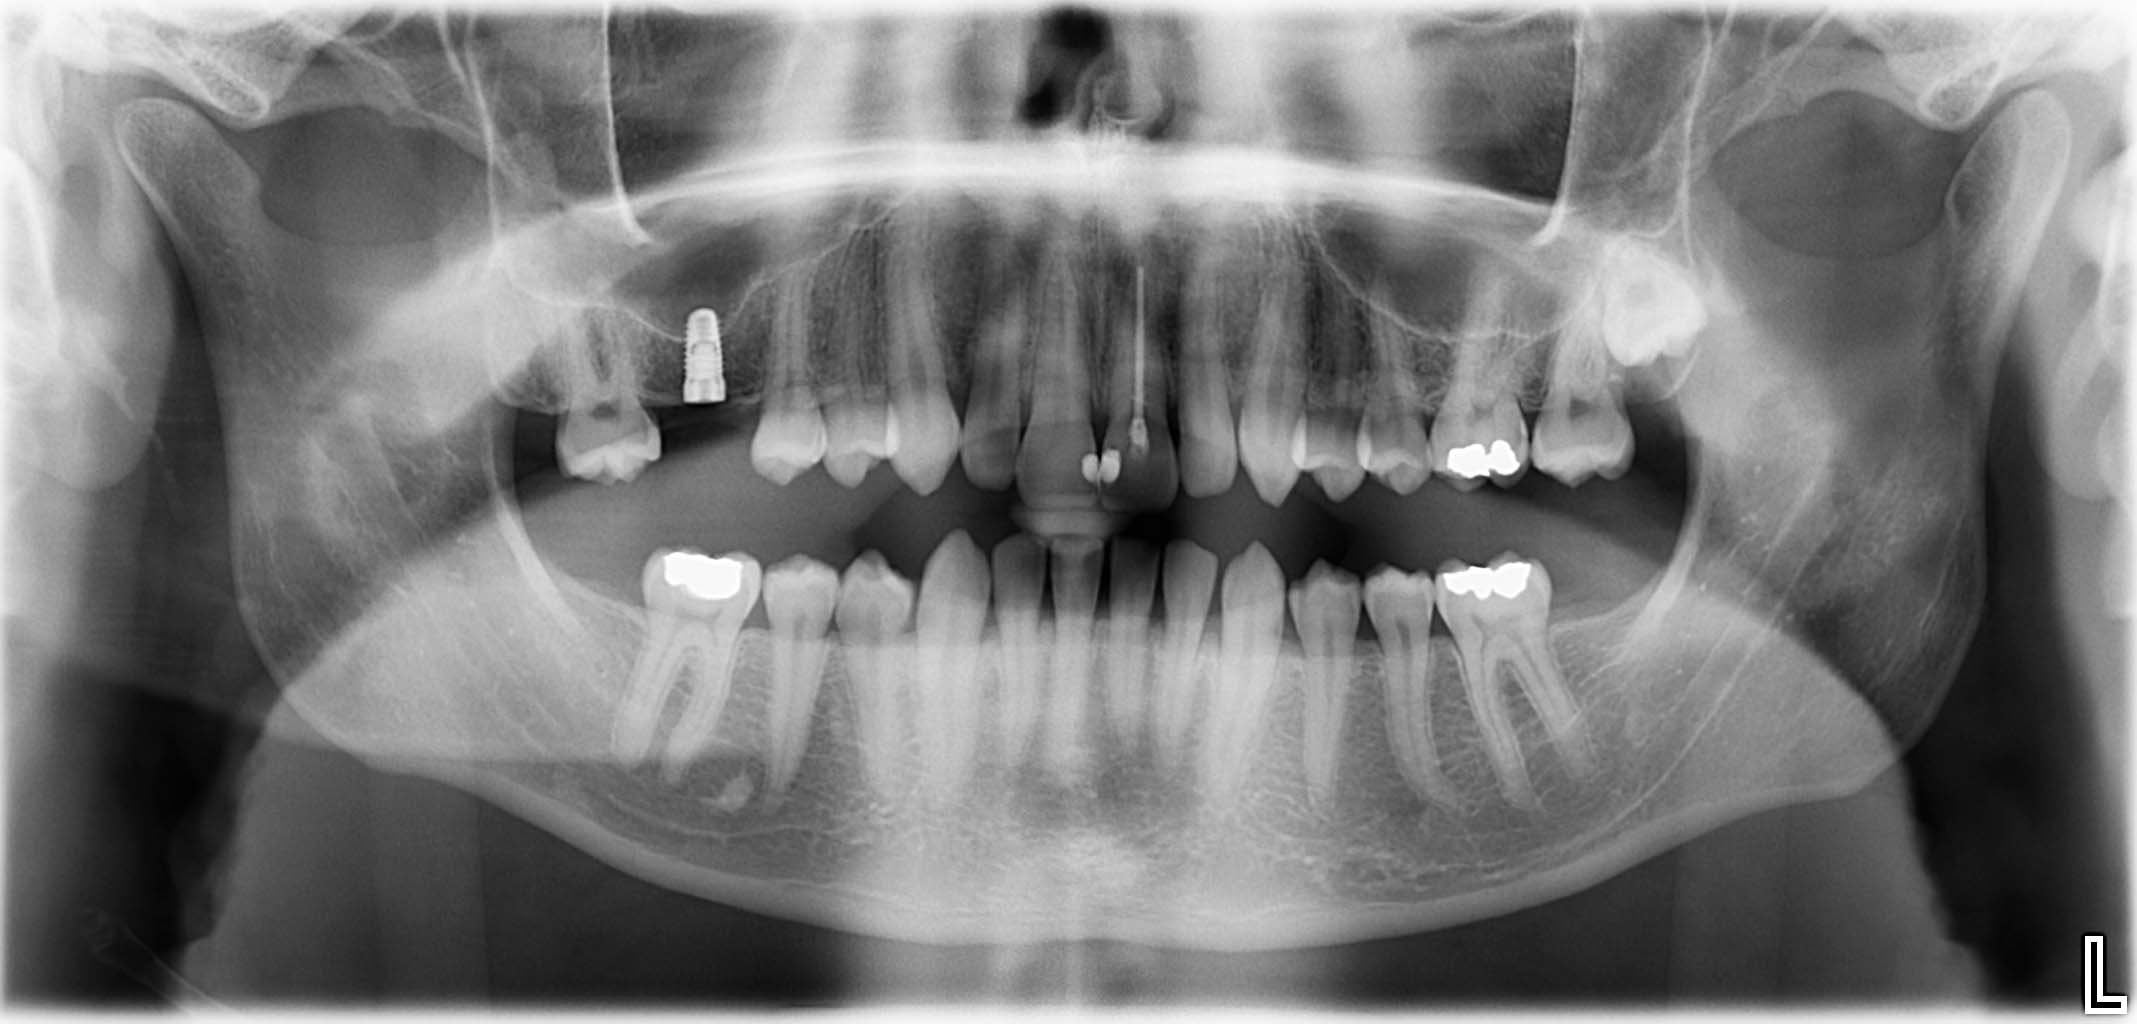

Ausgangssituation: Zahn 36 mit apikaler Beherdung, nicht erhaltungswürdig